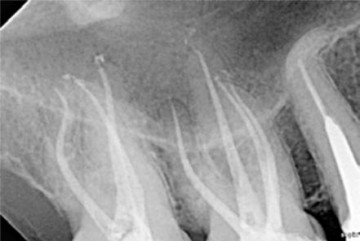

Preoperative x-ray of a 16 and a 17, both with deep caries and acute pulpitis.